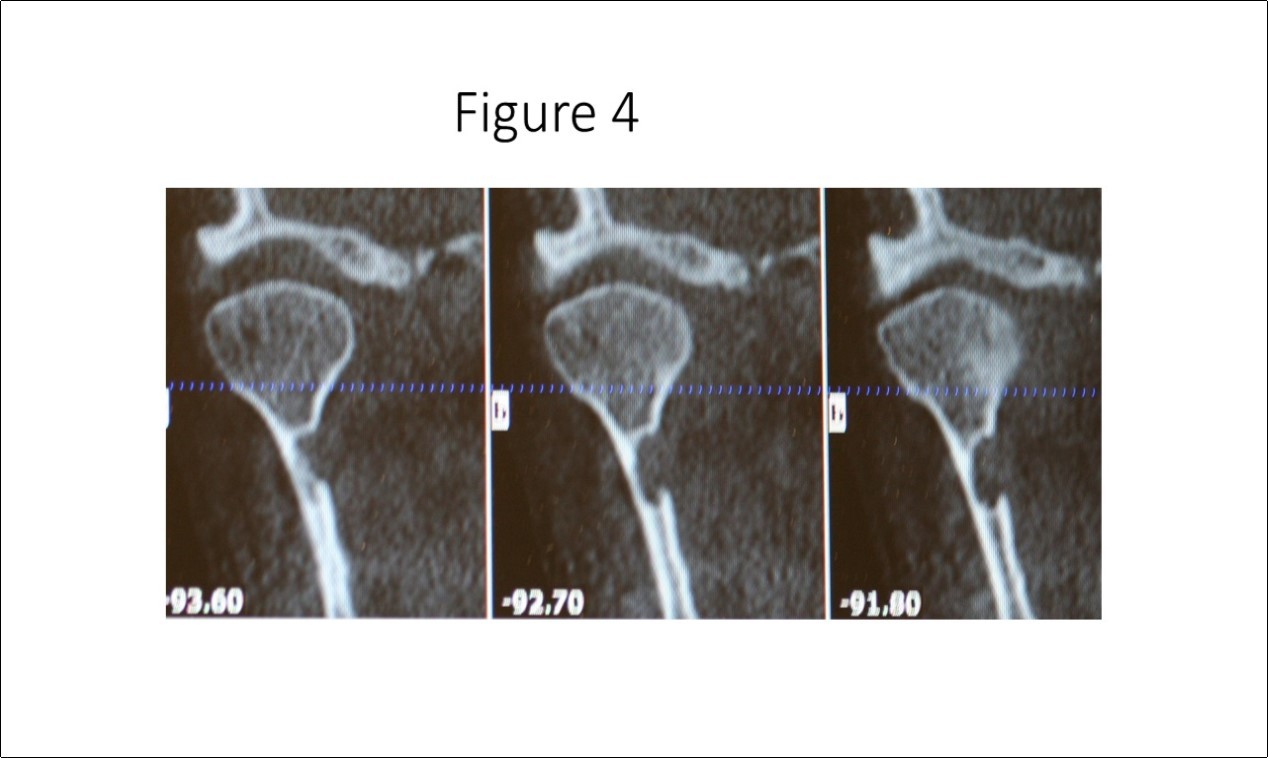

Maxillofacial examination was unremarkable. No facial swelling, masses or asymmetry was observed. The TMJ examination was normal. No pain or tenderness to digital palpation was observed in the right preauricular region. Oral examination of the patient was unremarkable. No trismus was observed as the maximal interincisive opening was greater than 40.0mm. No anterior or posterior open bite was observed. Imagining studies to rule-out intraosseous neoplastic lesions and arrive at a definitive diagnosis consisted of a panoramic radiograph and cone beam CT scan (120 kVp, 5 mA, 7.4 sec). Panoramic radiograph revealed a unilocular, well-circumscribed radiolucency in the right subcondyalar region of the mandible that was close to the posterior border of the condylar neck (Figure 2). Cone beam CT scan (i-CAT FLX, Imaging Sciences, Hatfield, PA) imaging revealed a well-defined unilocular, elliptical shaped radiolucent lesion on the medial surface of the right subcondylar neck of the mandible (Figure 3, Figure 4, Figure 5). The elliptical shaped unilocular lesion involved almost the entire horizontal dimension of the subcondylar neck (Figure 4). Figure 5 shows the three-dimensional CT scan reconstruction (i-CAT FLX, Imaging Sciences, Hatfield, PA) of the medial defect in the subcondylar region of the mandible. Based on knowledge of clinical head and neck anatomy and imaging studies, no treatment was indicated as the diagnosis was consistent with a variant of a Stafne bone cavity of the right subcondylar neck near the parotid gland and not a pathological condition. The patient was informed about the risk of condylar neck fracture due to the critical size of the SBC.

Figure 4.Cone beam CT TMJ sagittal views illustrate osseous defect on medial cortex. Note the thinness of the cortex that places the patient at risk for fracture of the condylar neck.